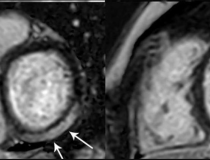

This photo gallery shows the variety of radiological presentations of COVID-19 (SARS-CoV-2) in medical imaging, including computed tomography (CT), radiograph X-rays, ultrasound, echocardiograms and magnetic resonance imaging (MRI). The radiology images show examples of typical COVID pneumonia in the lungs and the numerous complications the virus causes in the body in multiple organs, including the brain, kidneys, heart, abdomen and vascular system.

Ultrasound, especially hand-held ultrasound imaging devices, have become a primary imaging modality for novel coronavirus because of the ease to bag the device and sterilize it after use. CT and mobile X-ray systems are also used as front-line imaging systems for COVID-positive or suspected COVID patients.